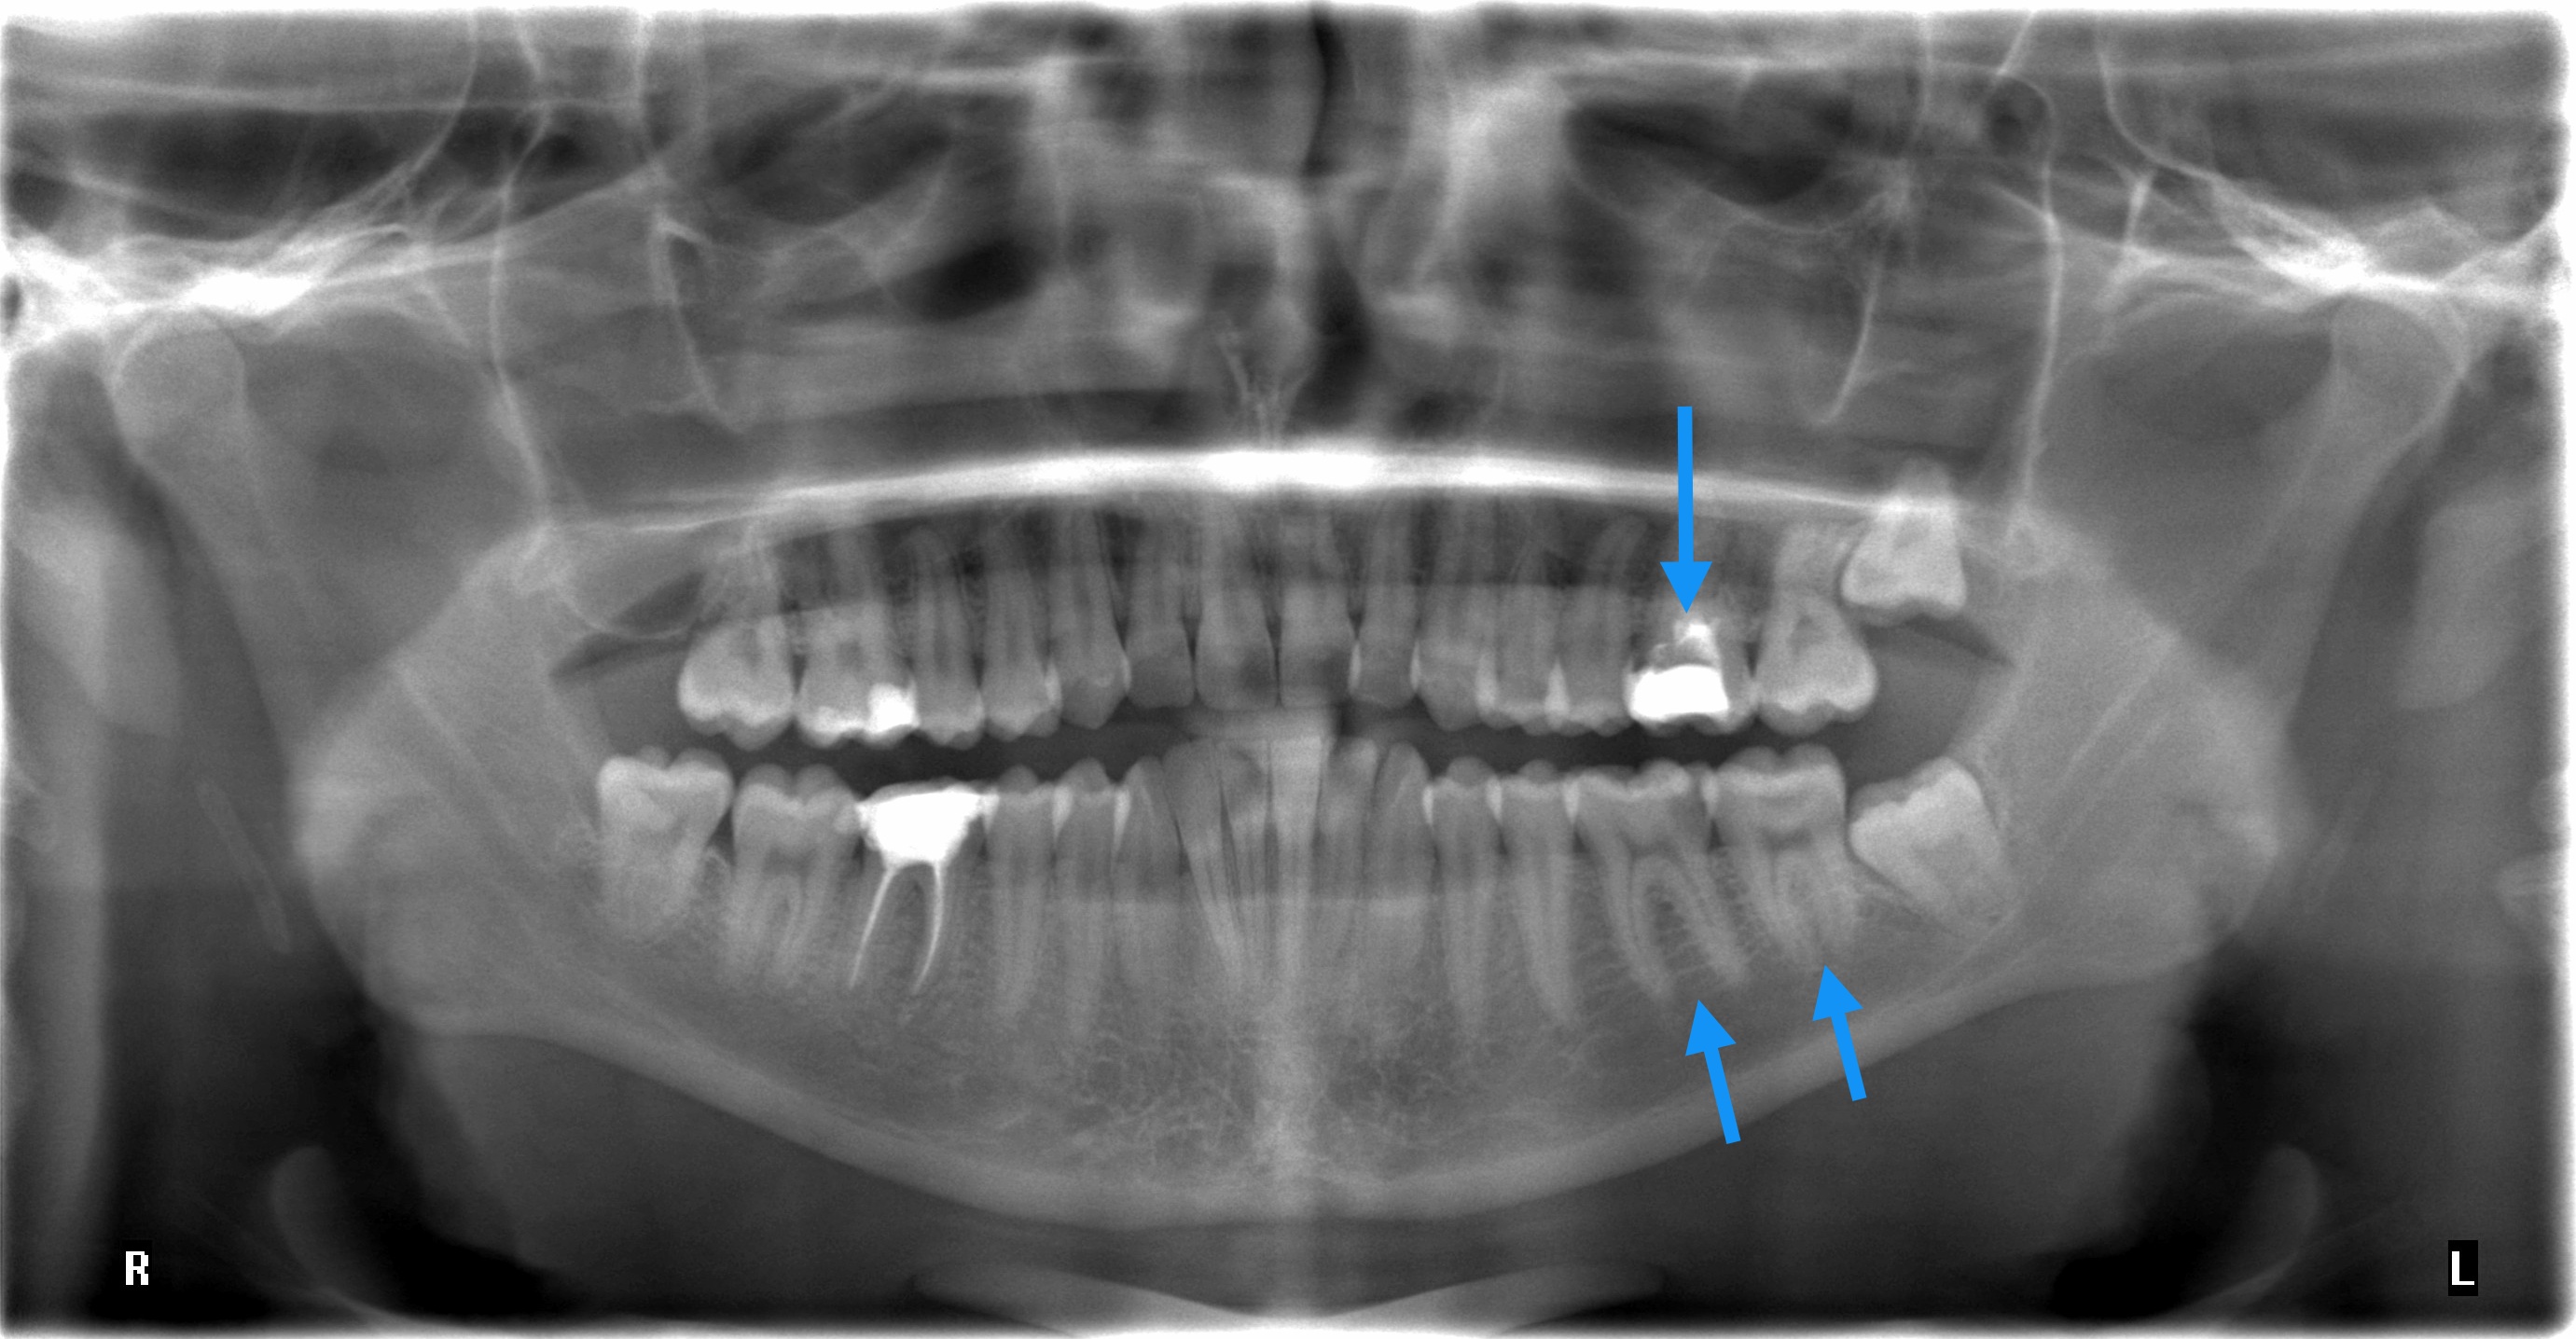

Ich hatte im März diesen Jahres eine starke Pulpitis mit submukösem Abszess des Zahnes regio 46. Es wurde eine Inzision zur Abszessentlastung durchgeführt, eine Drainage in Form einer Lasche eingelegt und eine Wurzelbehandlung durchgeführt, welche sich ca. über 4-5 Sitzungen streckte, bis der Zahn sich letztlich beruhigte und im Juni verschlossen wurde. Seitdem habe ich auch keine Schmerzen mehr beim kauen, kein pochen, pulsieren oder ähnliches. Jedoch habe ich gemerkt dass sich der Zahn bei Druck links und rechts an den Zahnwänden minimal im Zahnfach bewegen lässt, was auch spürbar ist. Mit bloßem Auge kaum sichtbar, nur bei genauerem hinsehen. Beim abklopfen der Zahnwände links und rechts verspüre ich einen leichten Schmerz. Ist das eine Indikation für eine fehlgeschlagene WB oder gibt es dafür eine andere Erklärung? Auf der Bissflügelaufnahme scheinen die Zahnwände nämlich schon recht dünn und die Füllung ziemlich groß. Hat das etwas damit zu tun? Was mir auch aufgefallen ist, ist das im Vergleich des Zahnes regio 36 die Füllung etwas niedriger ist.

P.S. Die mit blauen Pfeilen markierten Zähne im Panoramaröntgen wurden schon behandelt. Das Röntgen wurde am 28. Oktober dieses Jahr gemacht. Ebenfalls habe ich Ihnen einen Vergleich des Zahns regio 46 und 36 angehängt, damit Sie eventuell sagen können, ob die Füllung zu niedrig ist.

Würden sie Ihrer Einschätzung zufolge sagen, dass beide Weisheitszähne im linken Quadranten problemlos durchbrechen können oder sollten sie gezogen werden? Im Oberkiefer links habe ich des öfteren Schmerzen am Zahnfleisch, so als wäre dieses “Schleimhautbändchen” zu straff gespannt. Außerdem ist auch das Zahnfleisch darüber “weiß/heller”.